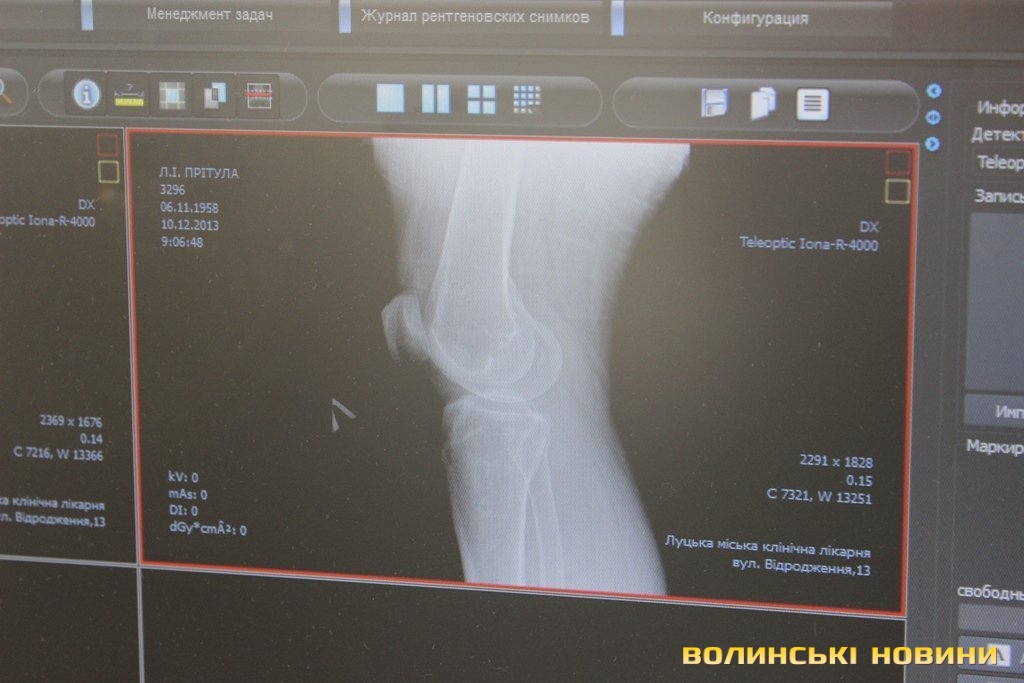

Травмовані заходять по черзі, але людей з різким болем пропускають першими. До слова, нещодавно тут почали працювати на новій цифровій апаратурі, для якої не потрібні одноразові плівки та й опромінювання менше. Рентген-лаборант Валентина Окопна каже: «Це пришвидшує прийом травмованих, бо ж не доводиться чекати, як в старинку, півгодини на результат сканування. Тепер рентгенівські результати миттєво отримує лікар на своєму комп’ютері, де може знімок збільшувати в рази і детально розглядати».